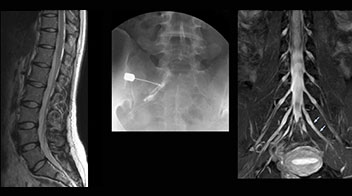

“In such case, we would then browse through axial T2-weighted MR images slice by slice and mentally reconstruct the actual situation based on both radiculography and MRI. Fortunately, NerveVIEW can now very well show nerve courses and presence of nerve compression or edema in one single image series.” “We have often seen NerveVIEW directly depict details of the nerve compression that were not observed by radiculography. Therefore, we think that with NerveVIEW we can reduce the number of invasive examinations, especially for some patients with lumbar plexus symptoms.”

“Before NerveVIEW, diagnosis by MRI alone was sometimes difficult, unless there was a strong suspicion based on clinical symptoms,” says Shoji Yabuki, MD, DMSc, Orthopedic surgeon at Fukushima Medical University School of Medicine. “This is why we routinely perform selective lumbosacral radiculography (nerve root block) and x-ray in such cases. However, radiculography can only depict nerves as far as the contrast agent reaches. When a nerve is distorted by compression, the contrast agent will not pass through this compressed area, preventing us from evaluating the full nerve compression.”

“The intra-luminal signal of veins, especially around the intervertebral space, can be suppressed well with NerveVIEW. As a result, we can easily observe the detailed nerve structure around the posterior ganglion,” he says. “This is why we use 3D NerveVIEW for intraforaminal stenosis and extraforaminal stenosis/herniation (lateral disc herniation). On the other hand, if herniation is suspected to exist inside the dorsal root ganglion (DRG), balanced TFE or ProSet-FFE is applied. NerveVIEW is not suitable for evaluating the median type of herniation.” The SE-EPI DWI-based method for MR neurography works well for large FOV exams like whole-body MRI, but focal examination of nerves is often limited by the attainable spatial resolution (both inplane and slice direction) and geometric distortion. “3D NerveVIEW achieves higher in-plane resolution – close to our other routine spine sequences – and the source images can be used instead of adding a fat-suppressed T2-weighted sequence,” Tanji says.

Implementing NerveVIEW without lengthening exam time “The source images of NerveVIEW exhibit a contrast similar to STIR or fat-suppressed T2-weighted images. So, in our neurography exams we are replacing the 2D T2-weighted coronal sequence with 3D NerveVIEW. With this, we add a lot of useful information without adding scan time. This is important for patients with severe lower extremity symptoms, as they often find it difficult to maintain still during the whole MRI examination, so the exam should be as short as possible.” “We have currently implemented 3D NerveVIEW on our Achieva 3.0T dStream MRI system only. Because the 3D NerveVIEW method is based on a background signal suppression technique, we decided to use the high SNR of our 3.0T MRI system for obtaining the best possible visualization of peripheral nerves,” says Tanji. “Where NerveVIEW of the lumbar plexus is currently used as a subroutine scan for patients with strong lower limb symptoms, its use for visualization of the brachial plexus, is currently limited to special cases such as schwannomas and neuritis, usually only 1 or 2 cases per month.”